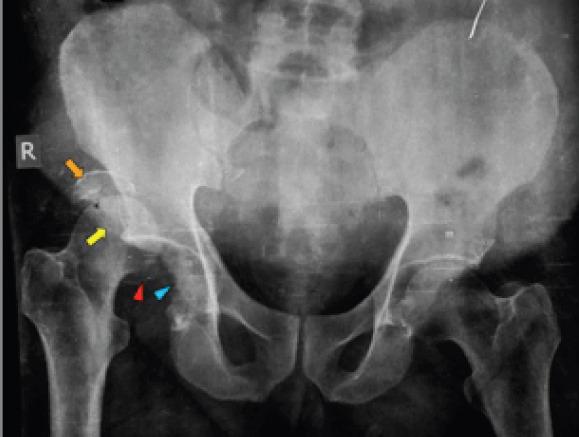

In this case report, we present a neglected 15 days old rare injury (Pipkin type IV femoral head fracture) in a 60 years old male patient that was given a trial of hip preservation surgery by ORIF through posterior (Kocher-Langenbeck) approach.

在本病例报告中,我们呈现了一名60岁男性患者,其15天前的罕见损伤(Pipkin IV型股骨头骨折)被忽视,通过后入路(Kocher-Langenbeck)进行切开复位内固定,尝试保髋手术。